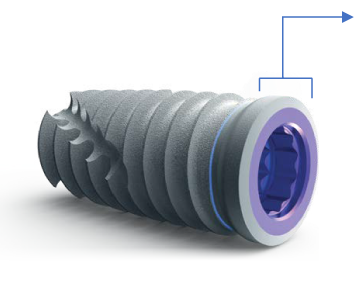

El implante T3® PRO de ZimVie® es la versión de nueva generación del implante cónico, diseñado para ofrecer una alta estabilidad primaria y posibilidad de función inmediata, reduciendo los tiempos de tratamiento sin sacrificar los resultados estéticos ni la salud ósea a largo plazo.

Su ingeniería incluye un núcleo totalmente cónico con roscado progresivamente más profundo hacia el ápice, lo que permite un contacto inicial hueso-implante alto y una inserción controlada. Además, cuenta con una superficie híbrida contemporánea, destinada a favorecer la osteointegración y mantener el nivel óseo periimplantario.

El sistema conserva la conexión interna Certain® compatible con la tecnología SureSeal™ y “Platform Switching”, lo que asegura un sello fuerte entre implante y pilar. Esto ayuda a minimizar micromovimientos o filtraciones, factores importantes para la durabilidad y salud del implante.

DISEÑO HÍBRIDO CONTEMPORÁNEO

Estabilidad primaria

El contacto inicial entre el hueso y el implante es el principal responsable de la estabilidad del implante. Las especificaciones de los implantes T3® de ZimVie® están sujetos a rigurosas tolerancias para ofrecer un íntimo ajuste entre el implante y la osteotomia, creando un sistema de implantes dentales que ayuda a conseguir estabilidad primaria.